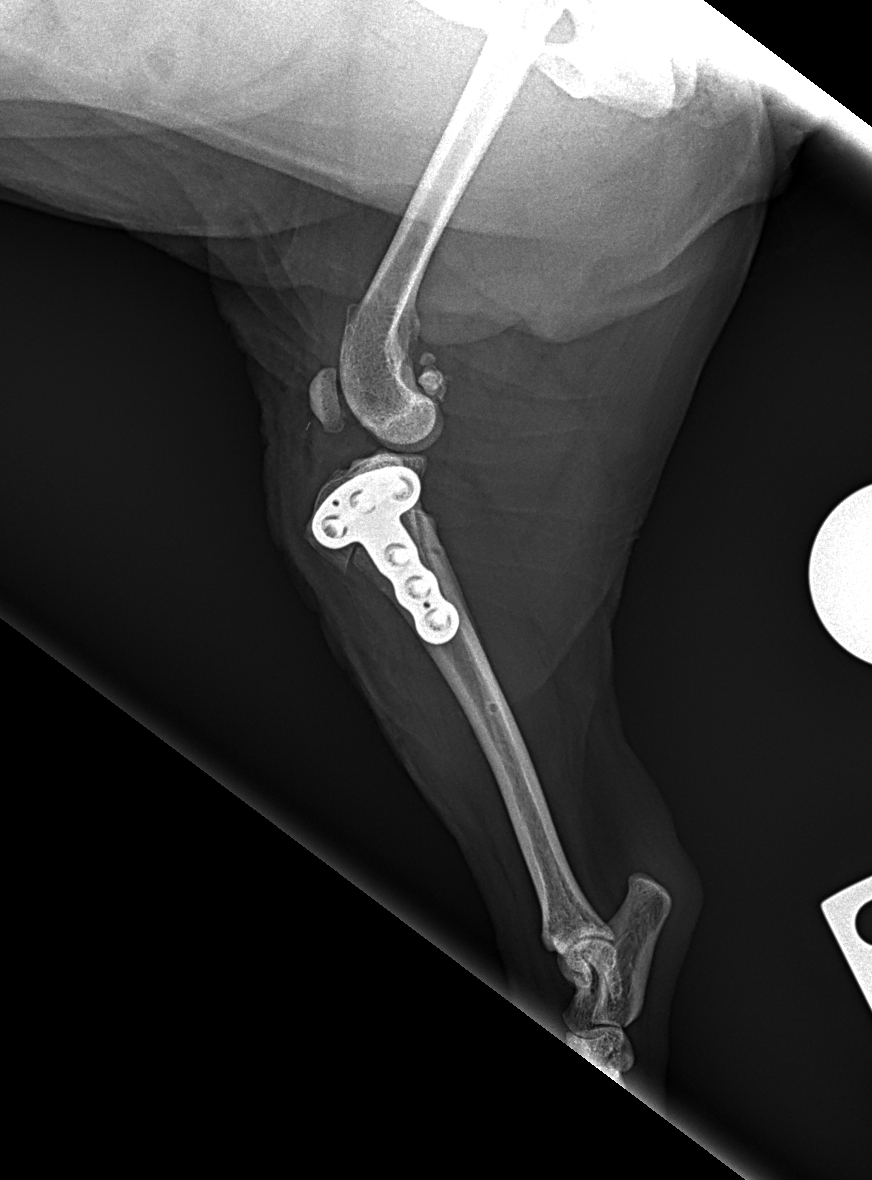

CBLO #205 超小型犬の前十字靭帯断裂に2.0 CBLOで対応しました。しばらく安静が必要です。 症例カテゴリー 放射線治療整形外科軟部組織外科脳神経外科内科腫瘍外科救急・集中治療リハビリテーション科腫瘍内科内視鏡科脳神経科呼吸器外科中医・漢方猫の腎移植循環器科